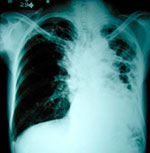

L Después del SIDA, la tuberculosis es la segunda causa de muerte por un agente infeccioso a nivel mundial. La tuberculosis, o TB, es una enfermedad contagiosa originada por una bacteria, un bacilo llamado Mycobacterium tuberculosis, que afecta principalmente los pulmones, aunque puede tener manifestaciones fuera de ellos. Esta enfermedad puede ser latente o activa. La TB latente es aquella que se encuentra en el organismo pero no produce síntomas ni se transmite, mientras que la TB activa sí lo hace. La Organización Mundial de la Salud (OMS) estima que una tercera parte de la población mundial tiene tuberculosis latente, sin que se manifieste, presente síntomas o pueda contagiarse. Estas personas tienen un 10% de riesgo de enfermar de tuberculosis a lo largo de su vida, no obstante, el porcentaje es mayor en población con un sistema inmune debilitado, como ocurre a causa del VIH, la diabetes, la desnutrición y el tabaquismo.

Los síntomas de la tuberculosis pulmonar activa incluyen tos con flemas (algunas ocasiones con sangre), dolores en el tórax, pérdida de peso, fiebre, debilidad y sudores nocturnos; durante el inicio de la enfermedad, estos síntomas pueden ser muy leves. Por esta razón, muchas veces los pacientes demoran en la búsqueda de atención médica, transmitiendo la enfermedad en ese tiempo: se calcula que durante un año, un enfermo de tuberculosis puede contagiar entre 10 y 15 personas por contacto estrecho.